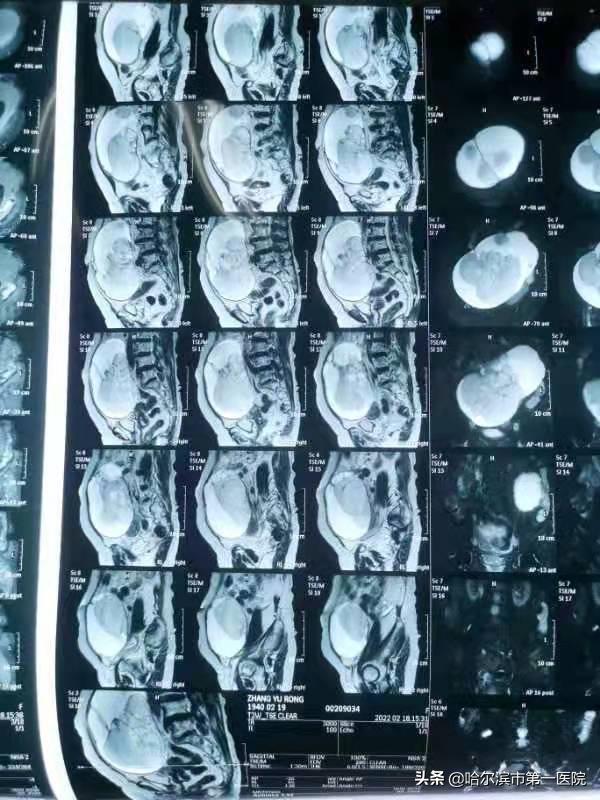

当张老太坐着轮椅来到妇二科田颖主任面前时,凭借多年的临床经验田主任一眼就判断这肯定是个“怪胎”,很可能是个巨大肿物占据老人腹腔,经查体发现肿物上缘达脐上3横指,相当于妊娠7个月。超声检查提示:盆腹腔巨大囊实性肿物,大小约25*20cm,完全证实了田主任之前的判断。可是老人年龄过高又伴有多种内科基础病,手术风险极大,田主任也有些犹豫,但主任看到老人痛苦的神情和家属的焦急与忐忑不安的表现时,田主任温柔又坚定说:“大娘,没关系,来我这儿吧,我们精准施救,一定能安全的排除病灶”。听到田主任语这番话语,家属们既温暖又感动像吃了“定心丸”一样悬着的心终于放下了。

入院后,田主任邀请心内科、麻醉科及血管外科专家联合会诊,充分评估了手术风险及术后血栓风险防治,充分考虑和论证了各种手术术式与手术方式的利弊,经与老人家属充分且良好的沟通后,田颖主任、赵霞、于婷等专家团决定为张老太施行(经脐部)单孔腹腔镜下双侧附件切除术。术中,从安全角度出发,考虑腹部囊肿巨大,无操作空间以及卵巢手术的无瘤操作原则,决定先将肿瘤部分提出切口外,放液、减少张力,缩小瘤体后再行切除。在麻醉医生的密切监护下,控制减张速度,患者组织极其脆弱,常一触即破,田主任抽丝剥茧般小心,寻找各个囊腔,充分保护,不让囊液外漏,分多次缓慢抽取粘性囊液多达3500毫升,在确切缝合结扎创面后,送还瘤体,电器械完整切除并取出双侧附件,手术过程顺利。术后,张老太在妇二科全体医护的精心照料下,恢复良好,术后6小时就下床活动了,张老太笑容又重新回到脸上,家属非常惊喜并对专家深表感谢。